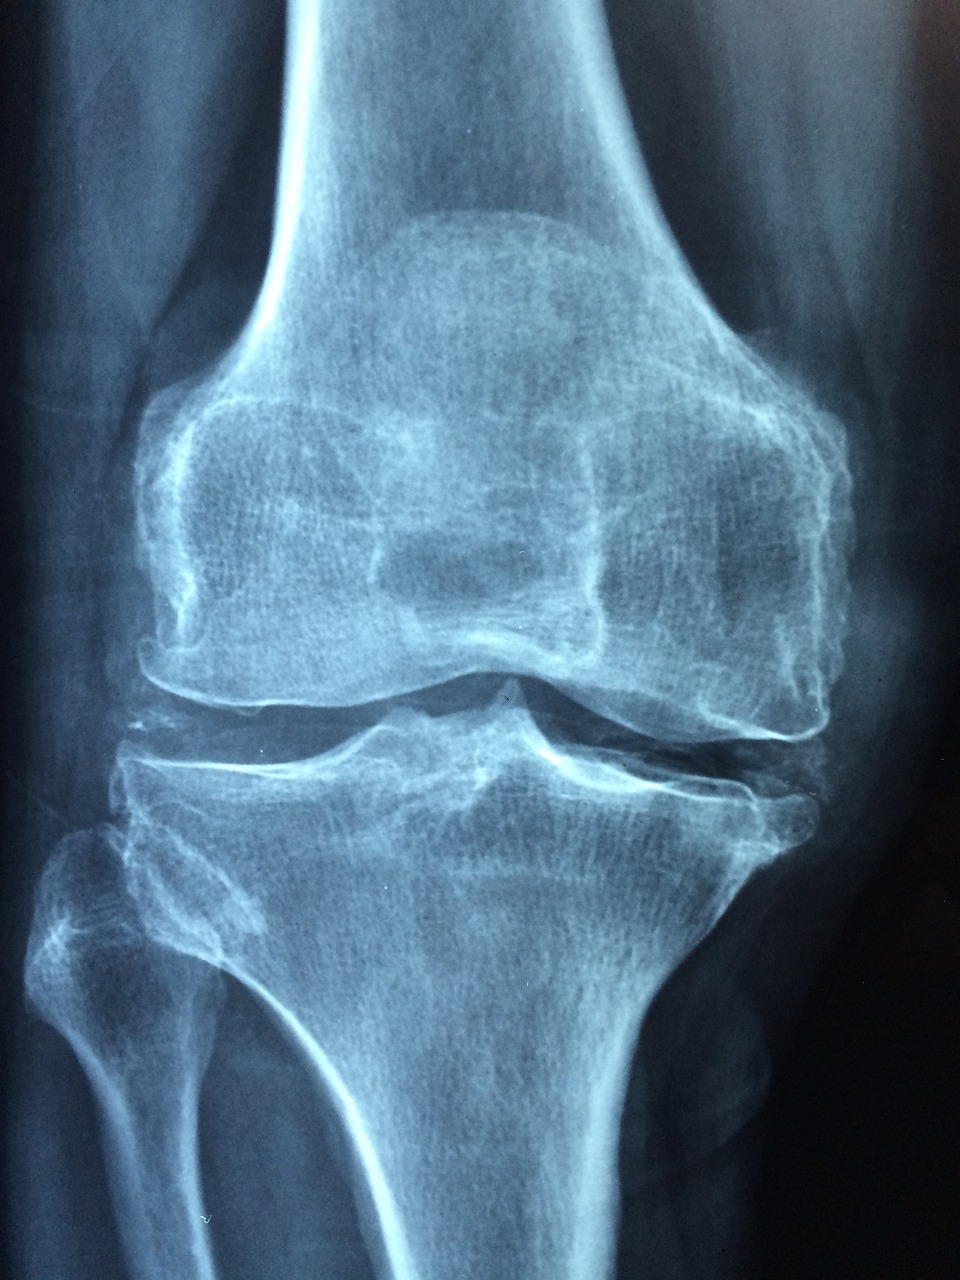

골다공증(osteoporosis)은 골량은 줄어드는 데 비해 구성(즉 골기질량에 대한 미네랄의 비율)은 변화하지 않는 전반적인 골장애입니다. 골소실은 폐경기 이후 가속화하여 90세까지 40% 정도의 골량이 소실될 수 있습니다. 세계보건기구연구팀은 골다공증을 젊은 성인에서 골무기질 밀도가 평균 최고치 이하 표준편차 2.5인 것으로 규정하고 있습니다. 골다공증은 골량과 미세구조상 골조직의 파괴로 뼈 자체가 부서지기 쉬워 골절이 발생할 위험이 높은 상태입니다.

골다공증은 골손실이 증상 없이 일어나기 때문에 '침묵의 병'이라고 불립니다. 따라서 골절이 일어나기 전에 증상이 나타나지 않습니다. 골다공증의 위험이 는 노인의 경우 골절이 일어나기 전에 골밀도를 측정하여 골다공증으로 인해 초래될 수 있는 각종 골절, 요통 및 척추측만증 등의 합병증을 예방해야 합니다.